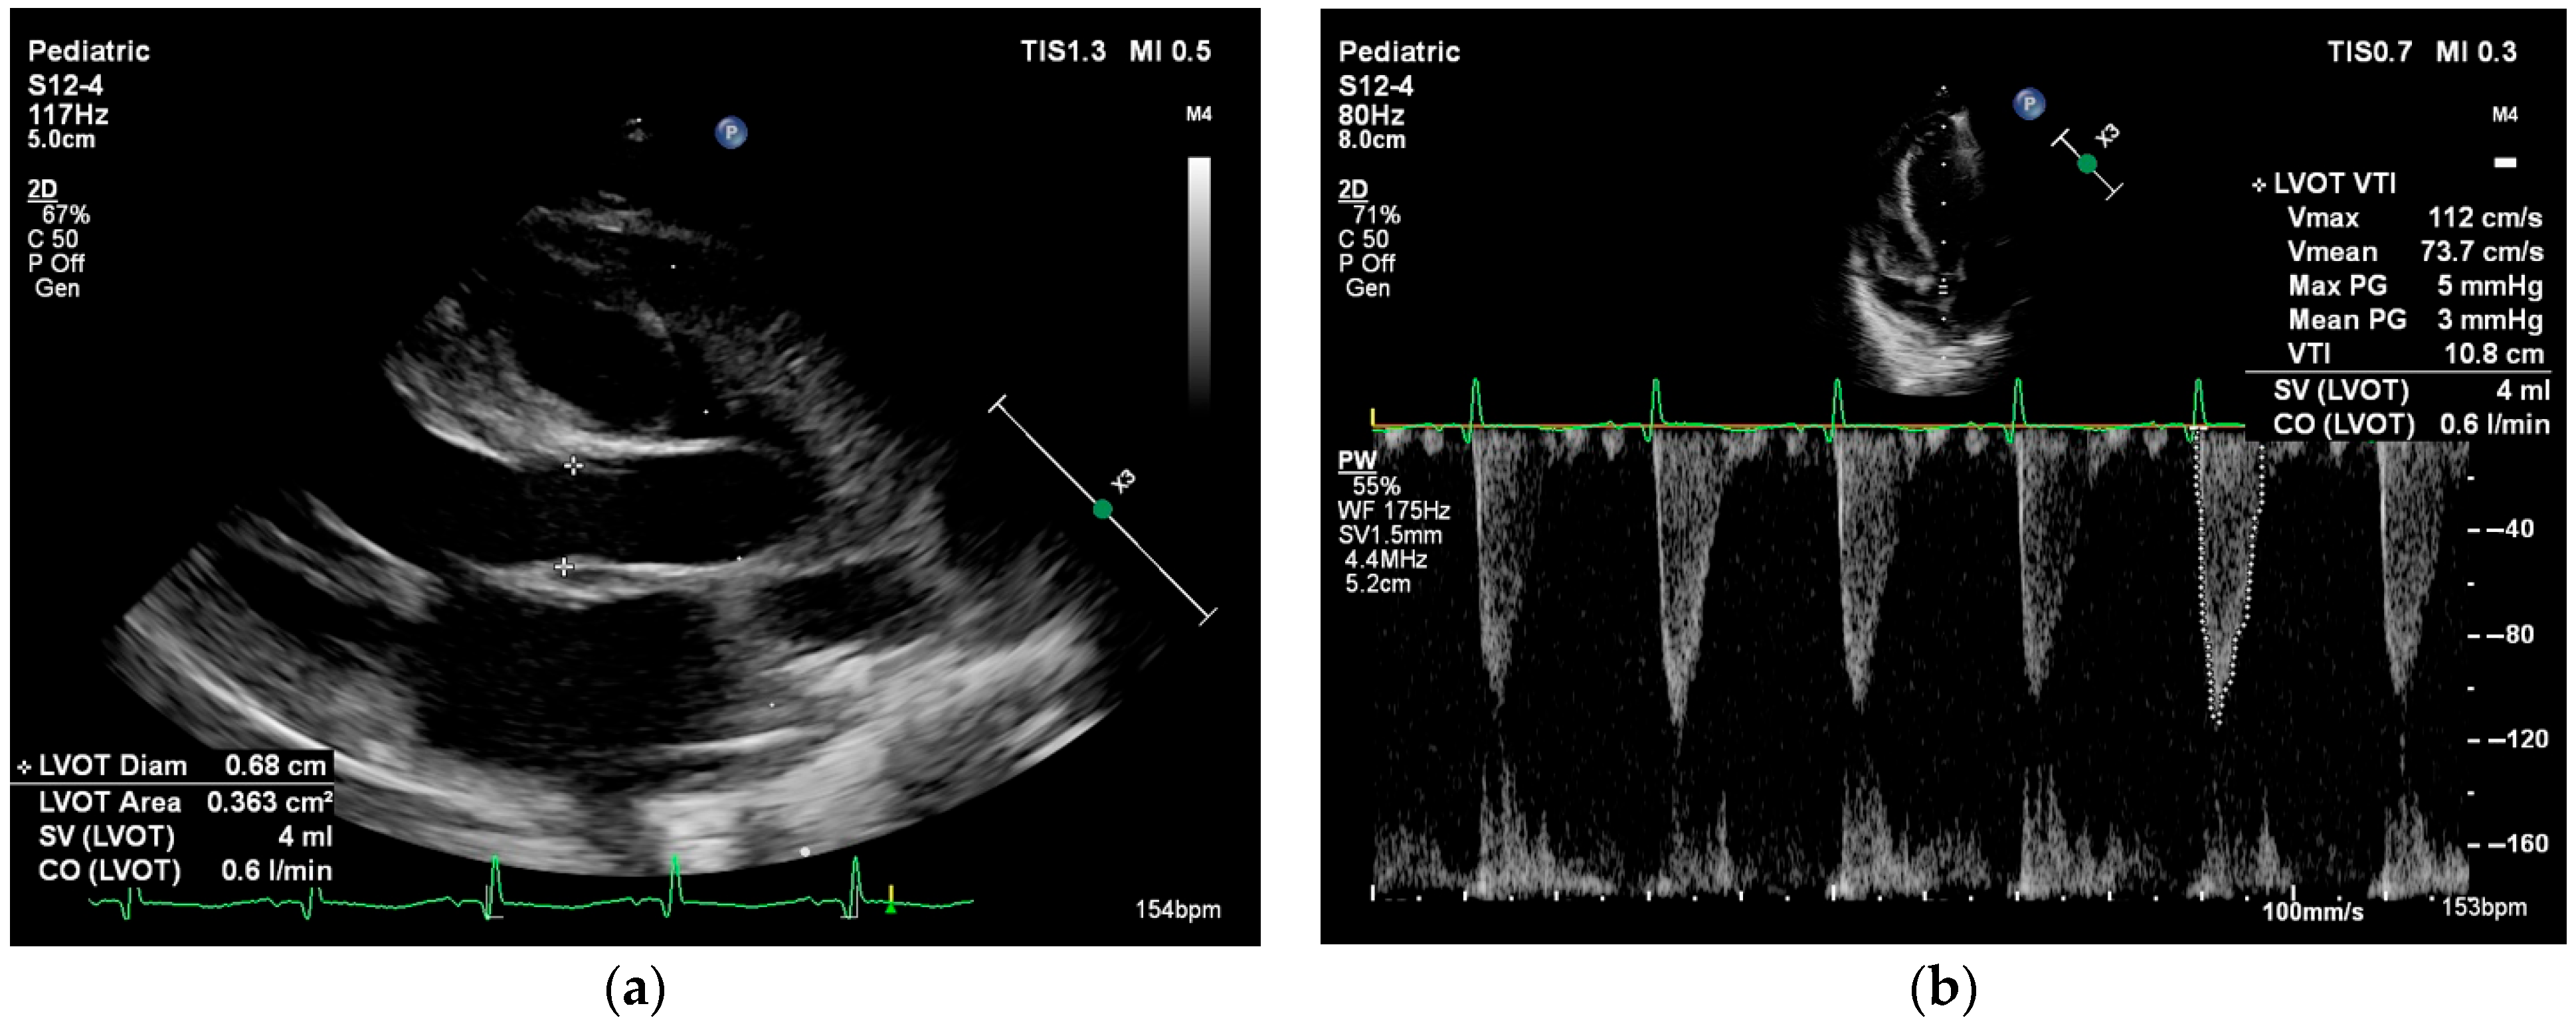

Systemic blood flow (left ventricular output, LVO) and pulmonary blood flow (right ventricular output, RVO) can be estimated by calculating the product of the Doppler flow velocity (velocity time integral, VTI), the cross-sectional area (CSA) of the left or right ventricular outflow tracts, and heart rate. In the presence of intra- or extracardiac shunts, LVO and RVO are not interchangeable. There are normative data for neonatal VTI and cardiac index, but these measurements are highly dependent on correct ultrasound probe positioning and accurate estimation of the outflow tract diameter (see Figure 2) [52].

Figure 2. Cardiac output measurement performed in the parasternal long axis view in a neonate with myocarditis. Cardiac output = stroke volume × heart rate. Stroke volume = velocity time integral × cross-sectional area. (a) Left ventricle outflow tract (LVOT) cross-sectional area = π × (LVOT diameter/2)2. (b) Velocity time integral is measured using pulsed wave Doppler at the level of the LVOT.